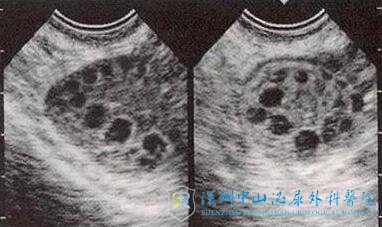

多囊卵巢综合征(PCOS)女性不孕的主要原因是少排卵或无排卵。事实上,90%有稀发月经或闭经的女性患者检查有PCOS。然而缺乏排卵并不是引起不孕症的原因之一,在确诊有多囊卵巢之后的女性还有生育需求可以选择试管婴儿;可是也有部分患者月经周期是规律的,但85%——90%的患者月经周期超过35天或每年少于9个月经周期。高雄激素血症和/或雄激素过量的临床证据(多毛症、痤疮、男性身体体征)在多达80%的多囊女性患者中存在。

一般多囊卵巢的患者会有排卵障碍的病症,往往由于过多卵泡的同时发育导致没有一个卵泡长成。而在试管婴儿治疗期间,只有先通过促排方案的调整才能够获得较多可用的卵泡。在超促排卵期间,医生还得考虑多囊的患者对促性腺激素的过度反应性。

卵巢过度刺激综合征(OHSS),是辅助生殖技术的主要并发症之一。它是人体对促排卵药物的过度反应,双侧卵巢多个卵泡发育,卵巢增大,毛细血管通透性增加,从而使得大量体液及白蛋白渗出到人体第三间隙而引起的一系列临床症状的并发症。其实,为了预防OHSS,患者还可以在促排期间多进食一些高蛋白的食物,取卵之后多喝一些冬瓜汤有助于排尿。